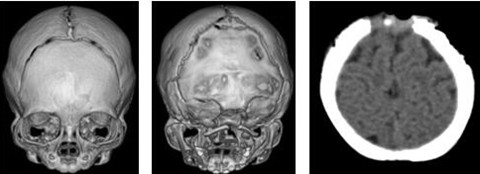

男婴,7月大,发现“出生后小头,前囟早闭5月”入院。入院查体:男婴表情自然,小头畸形,脑袋要比同龄小孩更长更窄:前后径偏小、额部颅腔小,头围约36cm,前囟、后囟已闭。能认熟人,可手持玩具,偶能独坐几秒钟,可控制颈部运动。诊断为颅缝早闭:狭颅症。

完善有关检查,排除手术禁忌症,小儿神经外科为患儿成功实施“额缝再造+前囟再造术”。术后患儿恢复良好,术后13天顺利出院。